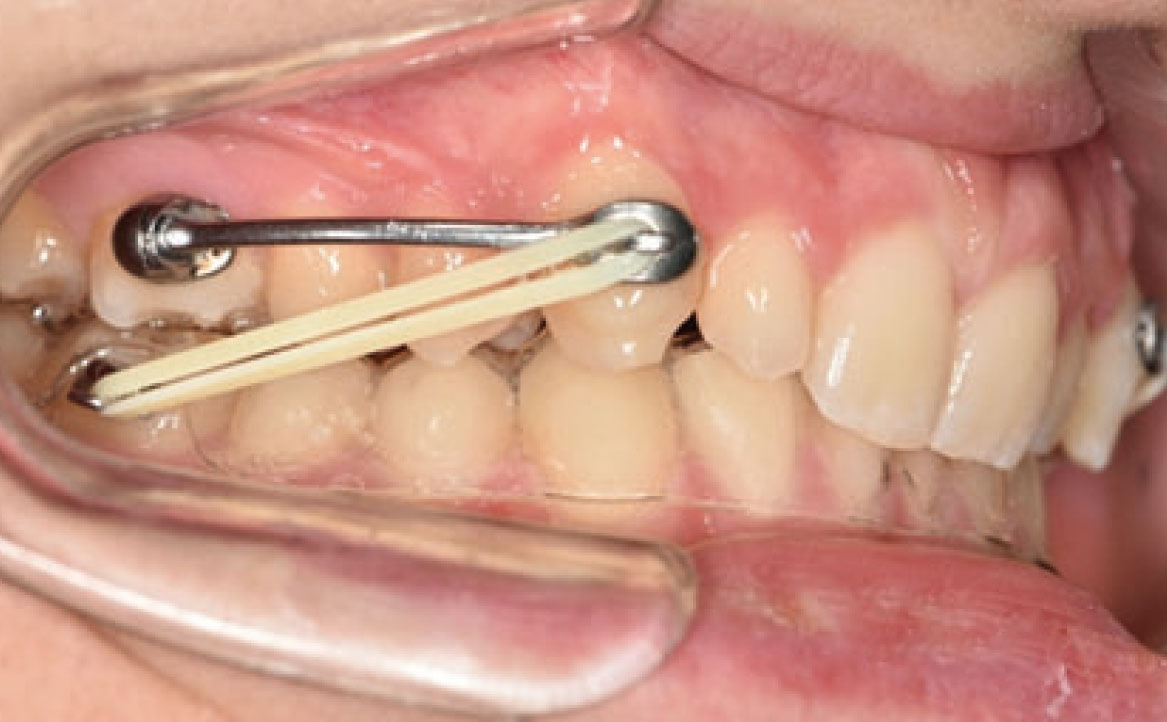

In primo luogo, sono stati prescritti entrambi gli esami radiografici ortodontici: OPT e teleradiografia latero-laterale del cranio (fig. 2a-b). Successivamente, in accordo con il genitore, è stata concordata una terapia ortodontica in due tempi. L’inizio della terapia è stato effettuato con Carriere Motion ed elastici di classe II, con l’obiettivo di migliorare la classe molare (fig. 2c-e).

Infatti, durante il primo controllo due mesi dopo, è stato osservato un miglioramento della classe molare (fig. 3a-c).